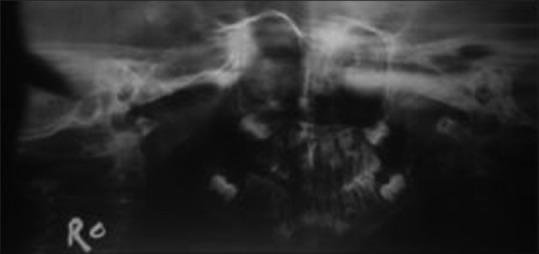

Unilateral condylar hyperplasia is an uncommon condition with unknown etiology which causes overdevelopment of condyle leading to facial asymmetry, mandibular deviation, malocclusion, and articulation dysfunction. Two Indian families with unilateral condylar hyperplasia are presented where the similar abnormality was also detected in one of their parents. The condylar hyperplasia in these two families indicates that mandibular condylar hyperplasia could be genetic in origin.

单侧髁突增生是一种病因不明的罕见病症,它会导致髁突过度发育,进而引起面部不对称、下颌偏斜、错牙合畸形及关节功能障碍。本文报告了两个患有单侧髁突增生的印度家族,在他们的一位家长中也检测到了类似异常。这两个家族中的髁突增生表明下颌髁突增生可能起源于遗传。